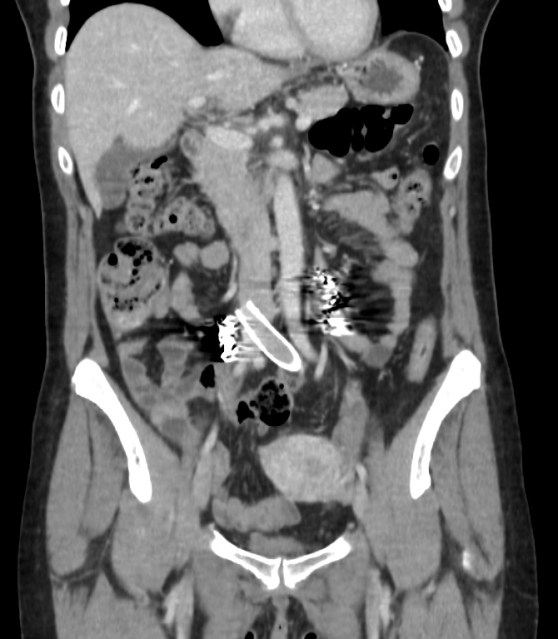

Lo que ves en estas imágenes que te voy a poner aquí son los hallazgos ecográficosque he podido visualizar hoy. Los voy a complementar con la correlación con las imágenes de TAC. En este caso específico con la eco solo se pudo corroborar los hallazgos del escáner, que a nivel anatómico arroja un mejor desarrollo de la anatomía regional implicada en el proceso.

En el corte axial de las imágenes 3 y 4 puedes ver la anatomía radiológica implicada. La relación es perfecta, y completamente explicativa de la situación resulta mediante el tratamiento quirúrgico. En ella la Arteria iliaca derecha para justo por encima de la Vena iliaca Izquierda con la capacidad de poder comprimirla.

Finalmente, imagen 5 y 6 que te enseñan el tratamiento aplicado a las gonadales de forma bilateral, embolizadas con material hiperecogénico en su interior que en la reconstrucción coronal del CT se objetiva como una imagen bilateral brillante lateral a los grandes vasos.